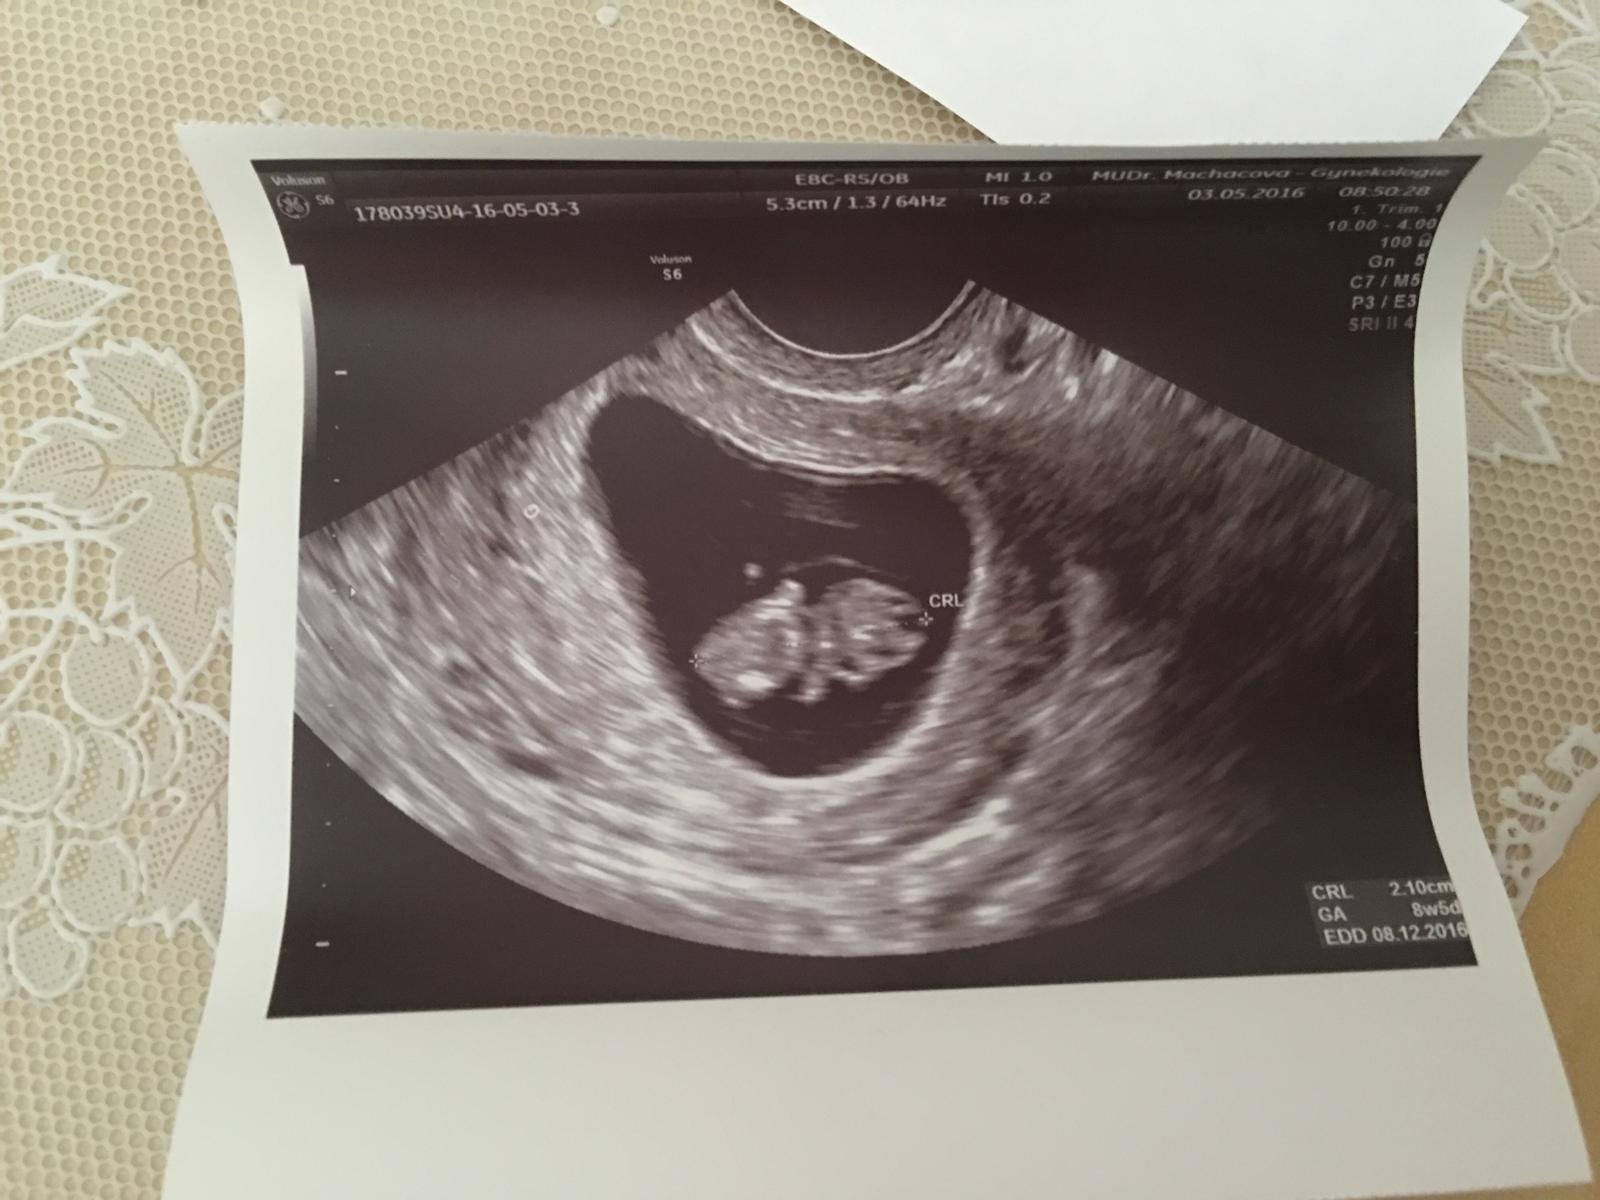

3.5. 2016 8tt+4 krááásně rosteme! Srdíčko máme už od 6tt+3 :) měříme 2,1 cm :) a maminka je spokojená 😊